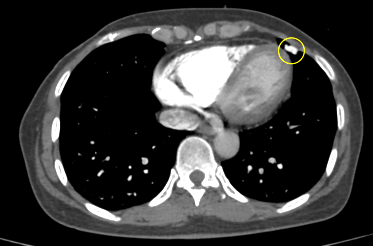

Công nghệ tim mạch Aheart

Phương pháp chỉnh sửa ECG

Hình ảnh lâm sàng